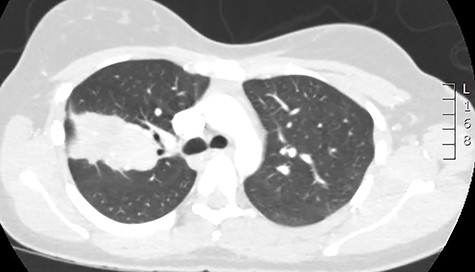

Initial investigations included a full blood panel with inflammatory markers (all within normal range) and a plain chest radiograph which demonstrated a mass in the right upper zone (Fig. 1). Computer tomography pulmonary angiogram (CTPA) scan demonstrated an 8 x 6.5 cm soft-tissue lesion within the right upper lobe (Fig. 2). This mass appeared to extend from the right hilum to the pleural surface and contained multiple small arterial branches. Her delivery date was brought forward pending further investigations. Positron emission tomography CT (PET-CT) demonstrated this lesion to be intensely fluorodeoxyglucose (FDG) avid (Fig. 3).

PET-CT demonstrating the right upper lobe lesion to be intensely FDG avid.